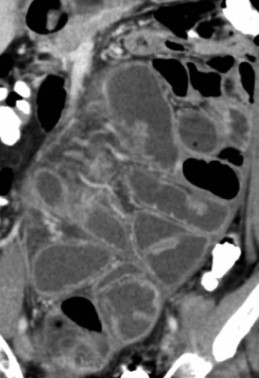

The two metastatic foci causing stenosis and bowel obstruction are clearly visible (Courtesy Dr. V. Penopoulos)